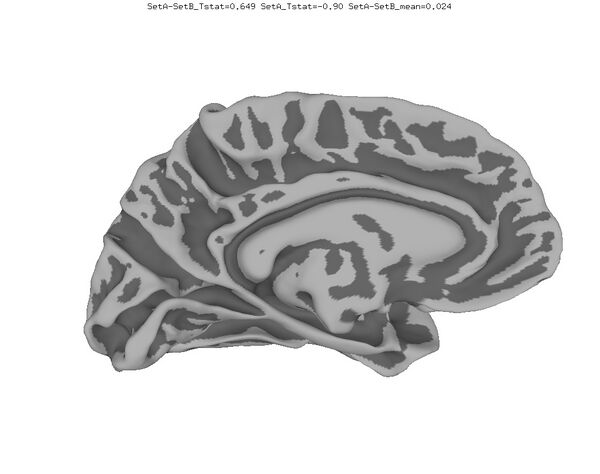

Anatomical Data

New

Old

Functional data of the Mouth vs. Eye contrast mapped to the average surface. It is hard to quantify the difference, but one way is to compare the maximum statistical values; with better intersubject alignment, these would presumably increase.

1. NEW: Max t-value for Mouth: 9.3 Eye:10.1 Eye vs Mouth: 5.6

2. OLD: Max t-value for Mouth: 7.9 Eye:8.8 Eye vs Mouth: 5.8

data from Zhu LL, Beauchamp MS. Mouth and Voice: A Relationship between Visual and Auditory Preference in the Human Superior Temporal Sulcus. Journal of Neuroscience 8 March 2017, 37 (10) 2697-2708; DOI: https://doi.org/10.1523/JNEUROSCI.2914-16.2017. Click here to download the PDF. Surface averages were not used in this paper so the bug did not affect the published results.